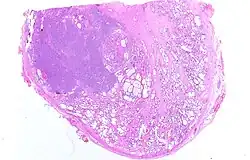

97 % aller Prostatatumoren sind Adenokarzinome, das heißt, sie entstehen aus entarteten Drüsenzellen. Ein Übergangsstadium zum manifesten Krebs wird als prostatische intraepitheliale Neoplasie (PIN) bezeichnet und entspricht einem Carcinoma in situ. Beim eigentlichen Karzinom kommen verschiedene histopathologische Wachstumsmuster vor, auch gleichzeitig nebeneinander: glandulär beziehungsweise azinär (drüsenartig), kribriform (siebartig) und solide. Das Ausmaß der Entdifferenzierung ist Grundlage des Gradings. 40–50 % der Tumoren liegen bei Diagnosestellung multifokal vor.[54]

Zum Grading des Prostatakarzinoms wird entsprechend der S3-Leitlinien zur Früherkennung, Diagnose und Therapie des Prostatakarzinoms der Gleason-Score verwendet.[70] Dabei wird nach dem histologischen Bild in der Stanzbiopsie das am schlechtesten differenzierte und das am häufigsten vorkommende Tumorgewebe mit Punktwerten zwischen 1 und 5 (zusammen also zwischen 2 und 10) bewertet und addiert. Bei einer bereits erfolgten Operation wird der häufigste und der am zweithäufigsten vorkommende Gleason-Grad in der gesamten Prostata addiert. Die beiden addierten Gleason-Grade müssen in der richtigen Reihenfolge und in der Stanzbiopsie in Prozent (des Gesamttumors und des gesamten gewonnenen Gewebes) angegeben werden. Ein Gleason-Score 3+4 stellt einen besser differenzierten Grad dar, als Gleason-Score 4+3, obwohl die Summe gleich ist. Ihre Summe wird in der Stanzbiopsie demnach anders interpretiert als im Operationspräparat. Eine Besonderheit ist, dass die Gleason-Grade 1 und 2 in der Stanzbiopsie nicht diagnostiziert werden können.[71]

Der Gleason-Score ist neben der Tumorgröße, dem Vorliegen von Lymphknoten- und Fernmetastasen (TNM-Klassifikation) ein wichtiger Prognosefaktor. Manchmal können zusätzliche Informationen zum Grading (zum Beispiel DNA-Zytometrie) hilfreich sein. Ein Gleason-Score kann nur bei Vorliegen eines nicht vorbehandelten Adenokarzinoms der Prostata erstellt werden, für Urothelkarzinome und neuroendokrine Tumoren wird ein anderes Grading-System benutzt.[70]